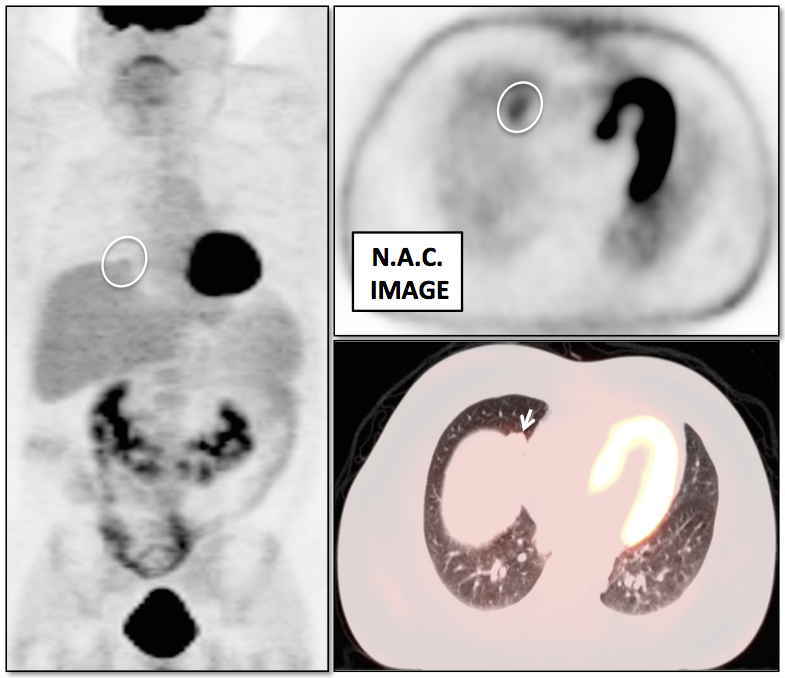

Lung Nodule Identification:

NAC images can occasionally be useful in identifying mild to moderately FDG-avid lung nodules, especially those located in the lung periphery or lung bases.